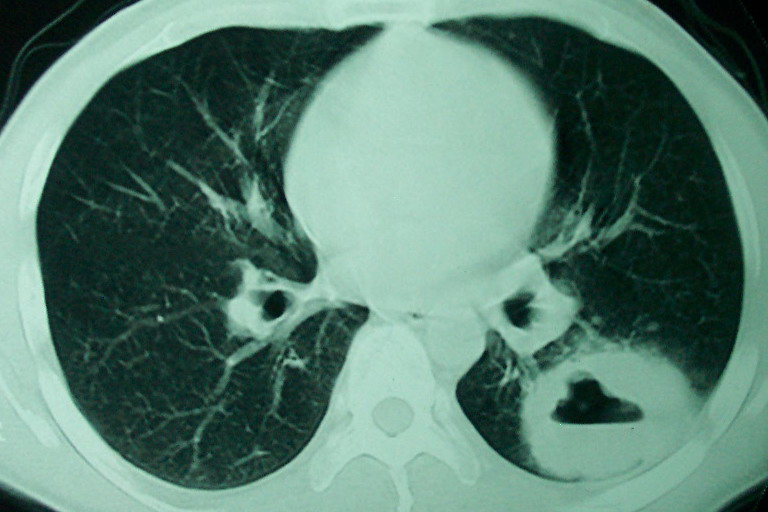

m      37y      发热   咳脓痰月余      ct肺脓肿但住院抗炎治疗后双肺内结节不知该如何解释

治疗后见左肺下野病灶较前缩小但双肺内结节影似无变化请较各位老师该如何下结论    治疗前wbc14.5 治疗后wbc 11.0

我看是不是可以两元化来解释,左肺下叶还是肺脓疡,而其余病灶考虑肺癌伴肺内转移,我看右肺上叶尖段病灶可见明显毛刺改变为原发病灶.

1、左下肺鳞癌伴两肺及纵隔淋巴结转移;

2、两上肺支扩伴慢性炎症。

左下肺病灶除了明显的厚壁空洞 气液平外,明显见壁结节,另两肺多发小结节,综合考虑:左下肺周围性肺癌伴肺内转移.

如果你仔细的同层面对比,你会发现所有的病灶均有比较明显的吸收、缩小。病变的形态,特别是脓肿的形态、壁的厚薄、内壁均有很大的变化,均在往好的方面发展。与临床症状、血像均符合,治疗效果比较显著,就是肺脓肿并双肺的化脓性炎症灶。